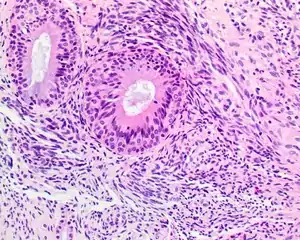

| A high-power view of a hematoxylin- and eosin-stained slide showing respiratory epithelial inclusions within a spindled cell neoplasm showing characteristics of a biphenotypic sinonasal sarcoma | |

- Infiltrative, highly cellular spindled cell neoplasm is poorly circumscribed and unencapsulated. Bone destruction or invasion is common. The cells show medium to long fascicles (nerve fibers), with a herringbone pattern. The cells are remarkably uniform with elongated nuclei. Delicate strands of intercellular collagen without ropy or dense deposition are seen. A very characteristic concurrent surface-type respiratory epithelial proliferation is found from the surface or in small cystic spaces around the cancer cells, often forming glands. The background may have a rich vascularity and usually has a small number of scattered lymphocytes. Extra growths or mitoses are rare, while necrosis, ulceration, and hemorrhage are usually absent.